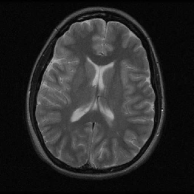

We present preliminary MRI reconstruction results using the proposed FRIST-MRI algorithm. The three complex-valued images and the corresponding k-space sampling masks used in this section are shown in Fig. 8, Fig. 9(a), and Fig. 9(b) 555The testing image data in this section were used and included in previous works [36, 53] with the data sources.. We retrospectively undersample the k-space of the reference images using the displayed sampling masks. We set , the sparsity level , and the other parameters were set similarly as for TL-MRI in [36]. We used a higher sparsity level for reconstructing Image 3, which worked well. To speed up convergence, lower sparsity levels are used in the initial iterations [36]. We compare our FRIST-MRI reconstruction results to those obtained using conventional or popular methods, including naive Zero-filling, Sparse MRI [17], DL-MRI [31], PBDWS [22], PANO [29], and TL-MRI [36]. The parameter settings for these methods are as mentioned in [36]. We separately tuned the sparsity parameter for TL-MRI [36] for reconstructing Image 3 666We observed improved reconstruction PSNR compared to the result obtained using the sparsity settings in [36].. The reconstruction PSNRs (computed for image magnitudes) for various approaches are compared in Table 6.

![]() |

First, the proposed FRIST-MRI algorithm provides significant improvements over the naive Zero-filling reconstruction (the initialization of the algorithm) with dB better PSNR on average, as well as dB better PSNR (on average) over the non-adaptive Sparse MRI reconstructions. Compared to recently proposed popular MRI reconstruction methods, the FRIST-MRI algorithm demonstrates reasonably better performance for each testing case, with an average PSNR improvement of dB, dB, and dB over the non-local patch similarity-based PANO method, the partially adaptive PBDWS method, and the adaptive dictionary-based DL-MRI method.

The proposed FRIST-MRI reconstruction quality is dB better than TL-MRI on average. As we followed a reconstruction framework and parameters similar to those used by TL-MRI [36], the quality improvement obtained with FRIST-MRI is solely because the learned FRIST can serve as a better regularizer for MR image reconstruction compared to the single adaptive square transform in TL-MRI. Figure 9 visualizes the reconstructions and reconstruction errors (magnitude of the difference between the magnitudes of the reconstructed and reference images) for FRIST-MRI and TL-MRI. The FRIST-MRI reconstruction error map clearly shows fewer artifacts, especially along the boundaries of the circles, compared to TL-MRI.